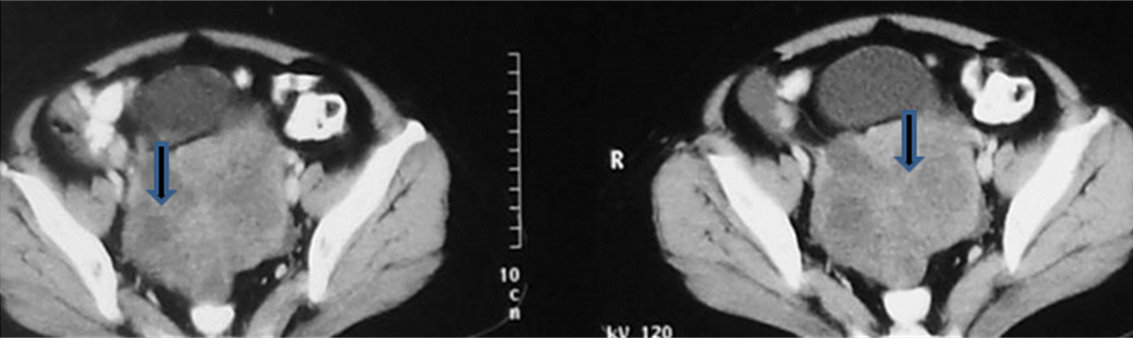

Metastases constitute about 5-15% of ovarian masses. Stomach, colon, breast, pancreas and lung are the most common primaries. Krukenberg tumours are ovarian metastases with mucus filled signet ring cells. They display bilateral, oval/ lobulated solid or predominantly solid with central necrosis. On CT/MR they show strong contrast enhancement. Non Krukenberg metastases appear similar to primary ovarian malignancy. They are usually bilateral and may be solid and cystic or complex lesion; may be multilocular and associated with ascites. Omental cake represents replacement of normal fat of omentum by a soft tissue density and the causes include peritoneal metastasis from carcinoma of colon, ovary, pancreas, stomach and breast and also from lymphoma, mesothelioma and tuberculosis of the peritoneum (Figures 18 & 19).

Figure 18: Krukenberg tumour from carcinoma of the breast.

Figures 19: 23y/F – Mucinous adenocarcinoma of stomach with deposits on ovaries - Krukenberg tumour.